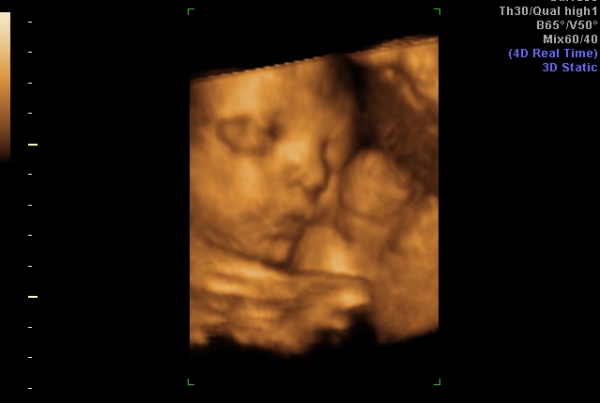

31 hetes